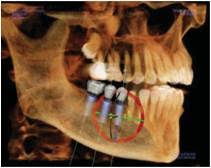

Dental cone beam computed tomography (CT) is a special type of x-ray machine used in situations where regular dental or facial x-rays are not sufficient. It is not used routinely because the radiation exposure from this scanner is significantly more than regular dental x-rays. See the Safety page for more information about x-rays. This type of CT scanner uses a special type of technology to generate three dimensional (3-D) images of dental structures, soft tissues, nerve paths and bone in the craniofacial region in a single scan. Images obtained with cone beam CT allow for more precise treatment planning.

Cone beam CT provides detailed images of the bone and is performed to evaluate diseases of the jaw, dentition, bony structures of the face, nasal cavity and sinuses. It does not provide the full diagnostic information available with conventional CT, particularly in evaluation of soft tissue structures such as muscles, lymph nodes, glands and nerves. However, cone beam CT has the advantage of lower radiation exposure compared to conventional CT.

- accurate placement of dental implants.